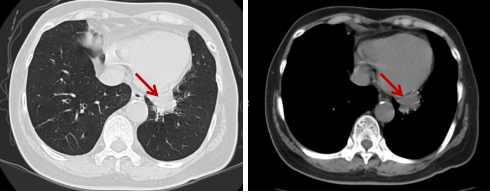

PET-CT(2023年11月16日): ①左肺下叶基底段软组织结节,糖代谢增高,考虑肺癌;②纵隔7组淋巴结糖代谢增高,考虑转移;③左侧额顶叶局部脑水肿改变,考虑转移可能。

图片2.png

PET-CT基线(2023年11月16日)